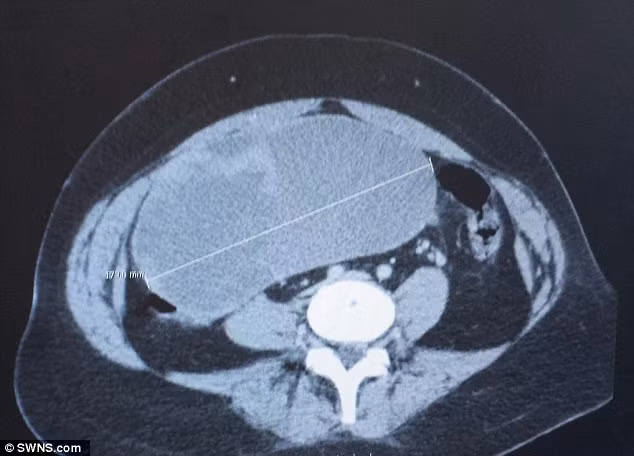

| Khối u to như quả bóng bầu dục trong tử cung. |